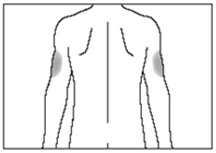

Wo sollte die Injektion bei mir erfolgen?

Die am besten geeigneten Stellen für eine Selbstinjektion sind:

·die Oberseite der Oberschenkel; und

·die Bauchdecke, mit Ausnahme des Bereichs um den Nabel herum (siehe Abbildung 7).

Wenn jemand anderes Ihnen die Spritze gibt, kann die Injektion auch auf der Rückseite der Arme erfolgen (siehe Abbildung 8).

Um zu verhindern, dass an einer Stelle Schmerzen auftreten, sollte die Injektionsstelle jeden Tag gewechselt werden.

7

8